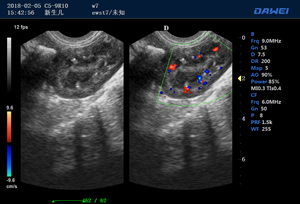

S90高端推車多普勒獸用彩超-動物寵物B超儀掃描圖 S90動物寵物B超儀檢測圖 S90多普勒獸用彩超